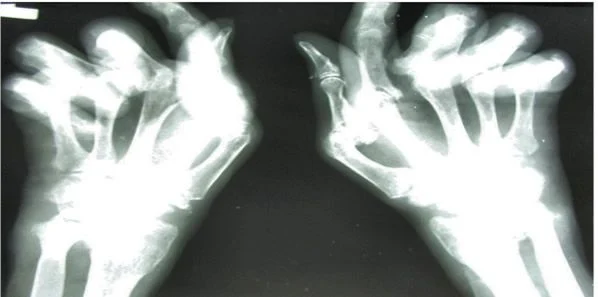

Rheumatoid arthritis is a chronic disease that affects nearly 1.3 million Americans. The disease occurs in women twice as often as men. TNF-alpha inhibitor drugs are used among RA patients but the response to these drugs varies from patient to patient.